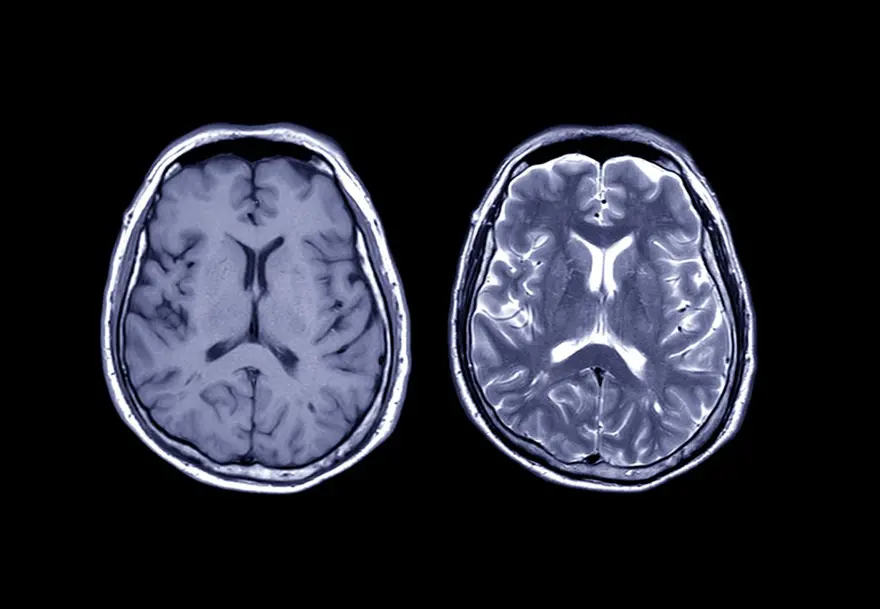

Danimarkalı bilim insanları, felç ve Alzheimer gibi beyin hastalıklarıyla mücadelede devrim yaratabilecek bir çalışmaya imza attı. Araştırmacılar, ilk kez insan beyninden alınan bir parçayı 12 saat canlı tutmayı başardı. Yeni gelişmenin yalnızca hayvanlarla mümkün olan çalışmaların ve deneylerin yapılmasına izin verdiği duyuruldu. Çalışmada, "Fareler üzerinde yapılan çalışmalar, bir iPhone'u tamir etmeye çalışırken Nokia 3310'a bakmak gibidir" denildi.

Ölümcül hastalıklar için yeni ilaçlar ve tedavilerin bulunmasına yardımcı olacak çığır açan bir çalışmada, ilk kez bir petri kabında* bir santimetrelik insan beyninin bir parçası canlı tutuldu.

Danimarka’da yer alan Kopenhag Üniversitesi'nden Emma Louise Louth liderliğindeki bir grup bilim insanı, bir hastanın korteksinden bir parça beyin dokusu çıkardı. Ardından bu dokunun hayatta kalmasını sağlamak için yeni bir süreç başlattı.

Bununla birlikte, araştırmacılar önce dokuyu soğutarak oksijenli kalmasını sağladı. Böylece hücreler canlı kaldı ve daha sonra küçük parçayı, beyin omurilik sıvısında bulunan aynı bileşenlerden oluşan (iyonlar ve mineraller) karışımına yerleştirdi.